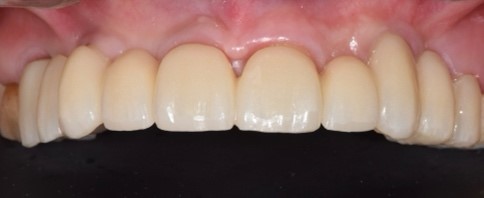

Il laboratorio odontotecnico utilizzava le più recenti tecnologie CAD/CAM per produrre una protesi dentale personalizzata e di alta qualità che si adattasse perfettamente e garantisse funzionalità ed estetica ottimali. Il concetto iPhysio® facilita il recupero automatico del profilo di emergenza sottogengivale da parte dell'odontotecnico per la realizzazione di soluzioni personalizzate sia con la protesi cementata che con la protesi avvitata (Fig. 5 a,b,c). La paziente tornava per il posizionamento del restauro finale in zirconio avvitato (Fig. 6 a,b).

Protesi finale

Fig. 6(a)

Protesi finale 2

Fig. 6(b) Protesi finale.